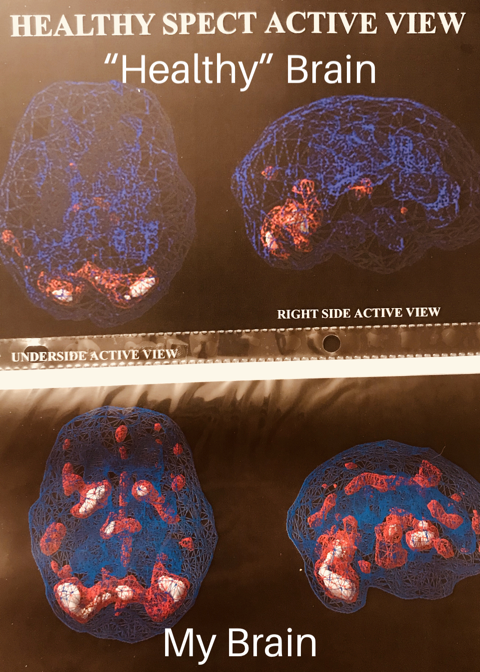

My parents took me to get brain scans done when I was 15. I have attached the images of a “normal” brain compared to my brain. It’s very intriguing. My brain looks like a damn Christmas tree. An average human uses 10% of their brain. As you can see, I use way more than 10%. I wouldn’t call this an illness. It has helped me immensely in my art. I’ve been drumming since I was, you guessed it, 13! It seems like that’s when my life really began. I taught myself for the most part aside from a beginning percussion class.